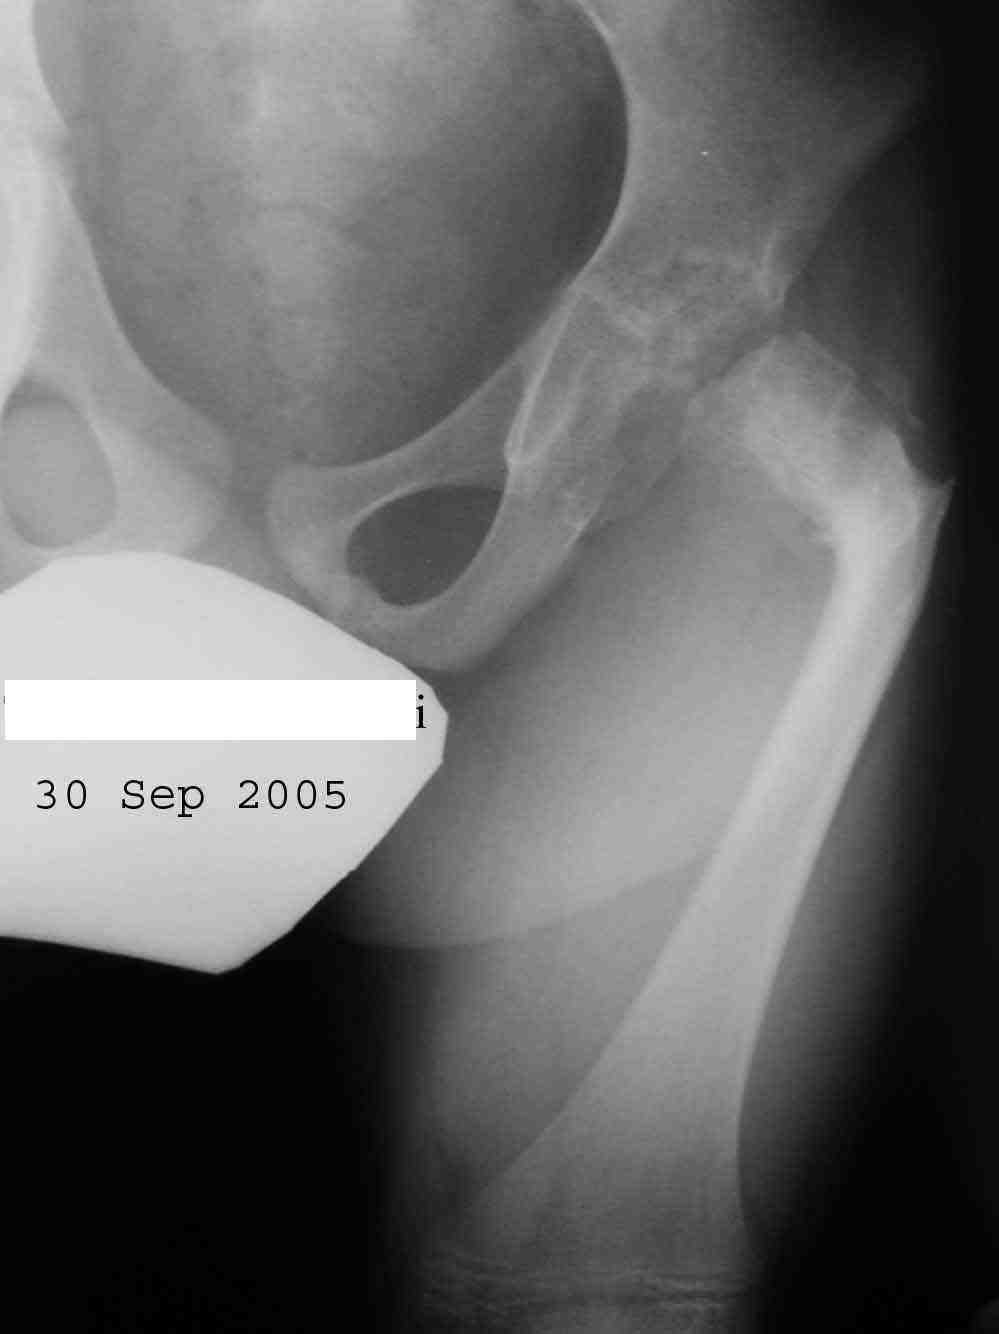

Извините за задержку(по техническим обстоятельствам) еще просим извинения за ошибки (трудный перевод). Больной с врожденной гипоплазией проксимальной части бедра, с ацетабулярной дисплазией. В 6 лет первая операция по стабилизации тазобедренного сустава прилагаю Рг. К нам обратился в следующей ситуацией:укорочение на 26см нижней конечности, соха flecta - 45 °.подвижной до 100°, genu flexum 25-30° мобильный до 90°. Активность мышц бедра- очень слабое, мышцы голени и сама голень отстающей в развитии. В настоящее время пациент ходит самостоятельно с протезом. Спасибо всем еще раз за присланные варианты лечения.Rx при рождении:ниже

Rx на сегодняшнии день